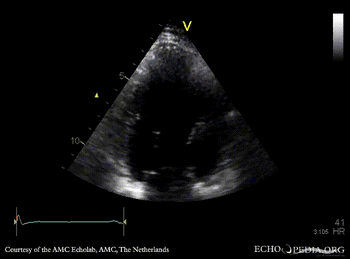

| Courtesy of: AMC Echolab, AMC, The Netherlands | |

| A4CH: apical akinesia | A2CH |